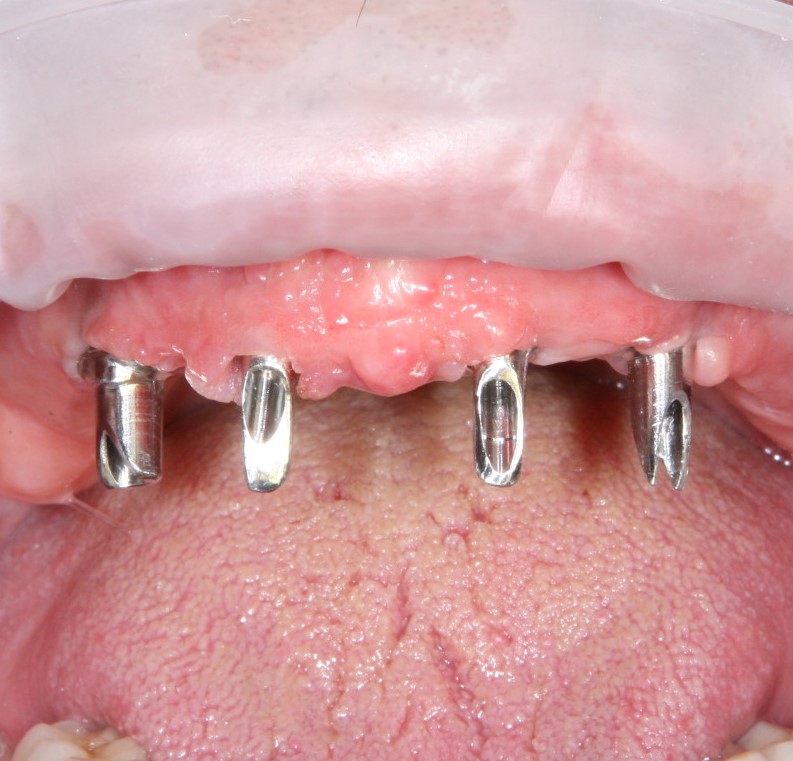

Трансгингивальные импланты, в отличие от всех остальных, имеют выраженную «чрездесневую» часть в виде полированной шейки:

Служит она примерно той же цели, что и переключение платформ. Кроме того, такие импланты не требуют отдельных формирователей и абатментов, поэтому очень удобны, когда речь идет об экономном, но, при этом, качественном лечении.

Конечно, наличие трансгингивальной части накладывает серьезные ограничения по установке трансгингивальных имплантов. В частности, их почти не используют в эстетически значимой зоне, они очень требовательны к правильному позиционированию и биотипу слизистой оболочки. Зато идеальны для фиксации условно-съемных конструкций при тотальном отсутствии зубов:

Из-за узких показаний к применению, трангингивальные импланты на рынке встречаются нечасто. Наверное, первым приходит на ум Straumann TL, XiVE TG, Zimmer Spline и т. д.